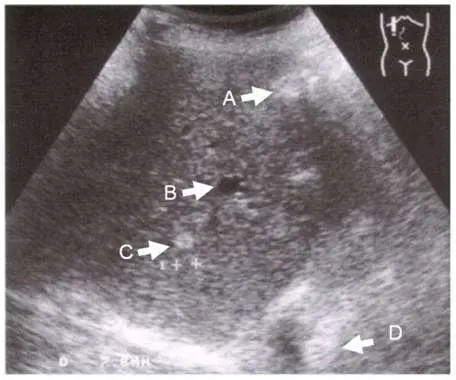

本圖為肝臟超音波(B-mode ultrasound)影像,呈現右上腹掃描的肝臟實質。影像右上角標示有人體方位圖示,協助定位。圖中以 A、B、C、D 四個白色箭號分別標記四個不同的肝臟病灶,需逐一判讀其超音波特徵:

A 箭號所指病灶:位於肝臟較上方淺層區域,呈現高回音(hyperechoic)表現,回音較周圍肝實質明亮,邊界可辨識,形態均勻。此高回音特徵最常見於肝血管瘤(hepatic hemangioma)——典型的超音波表現為均勻高回音、邊界清楚的小型病灶。不符合單純囊腫的無回音標準。

B 箭號所指病灶:位於肝臟中層區域,呈現完全無回音(anechoic)的圓形暗色病灶。其關鍵特徵包括:邊界清晰銳利(sharp well-defined border)、壁薄而光滑(thin smooth wall,幾乎不可見)、內部完全無回音(completely anechoic)、後方可見音波增強(posterior acoustic enhancement)。這四項特徵完整符合單純肝臟囊腫的超音波診斷標準。